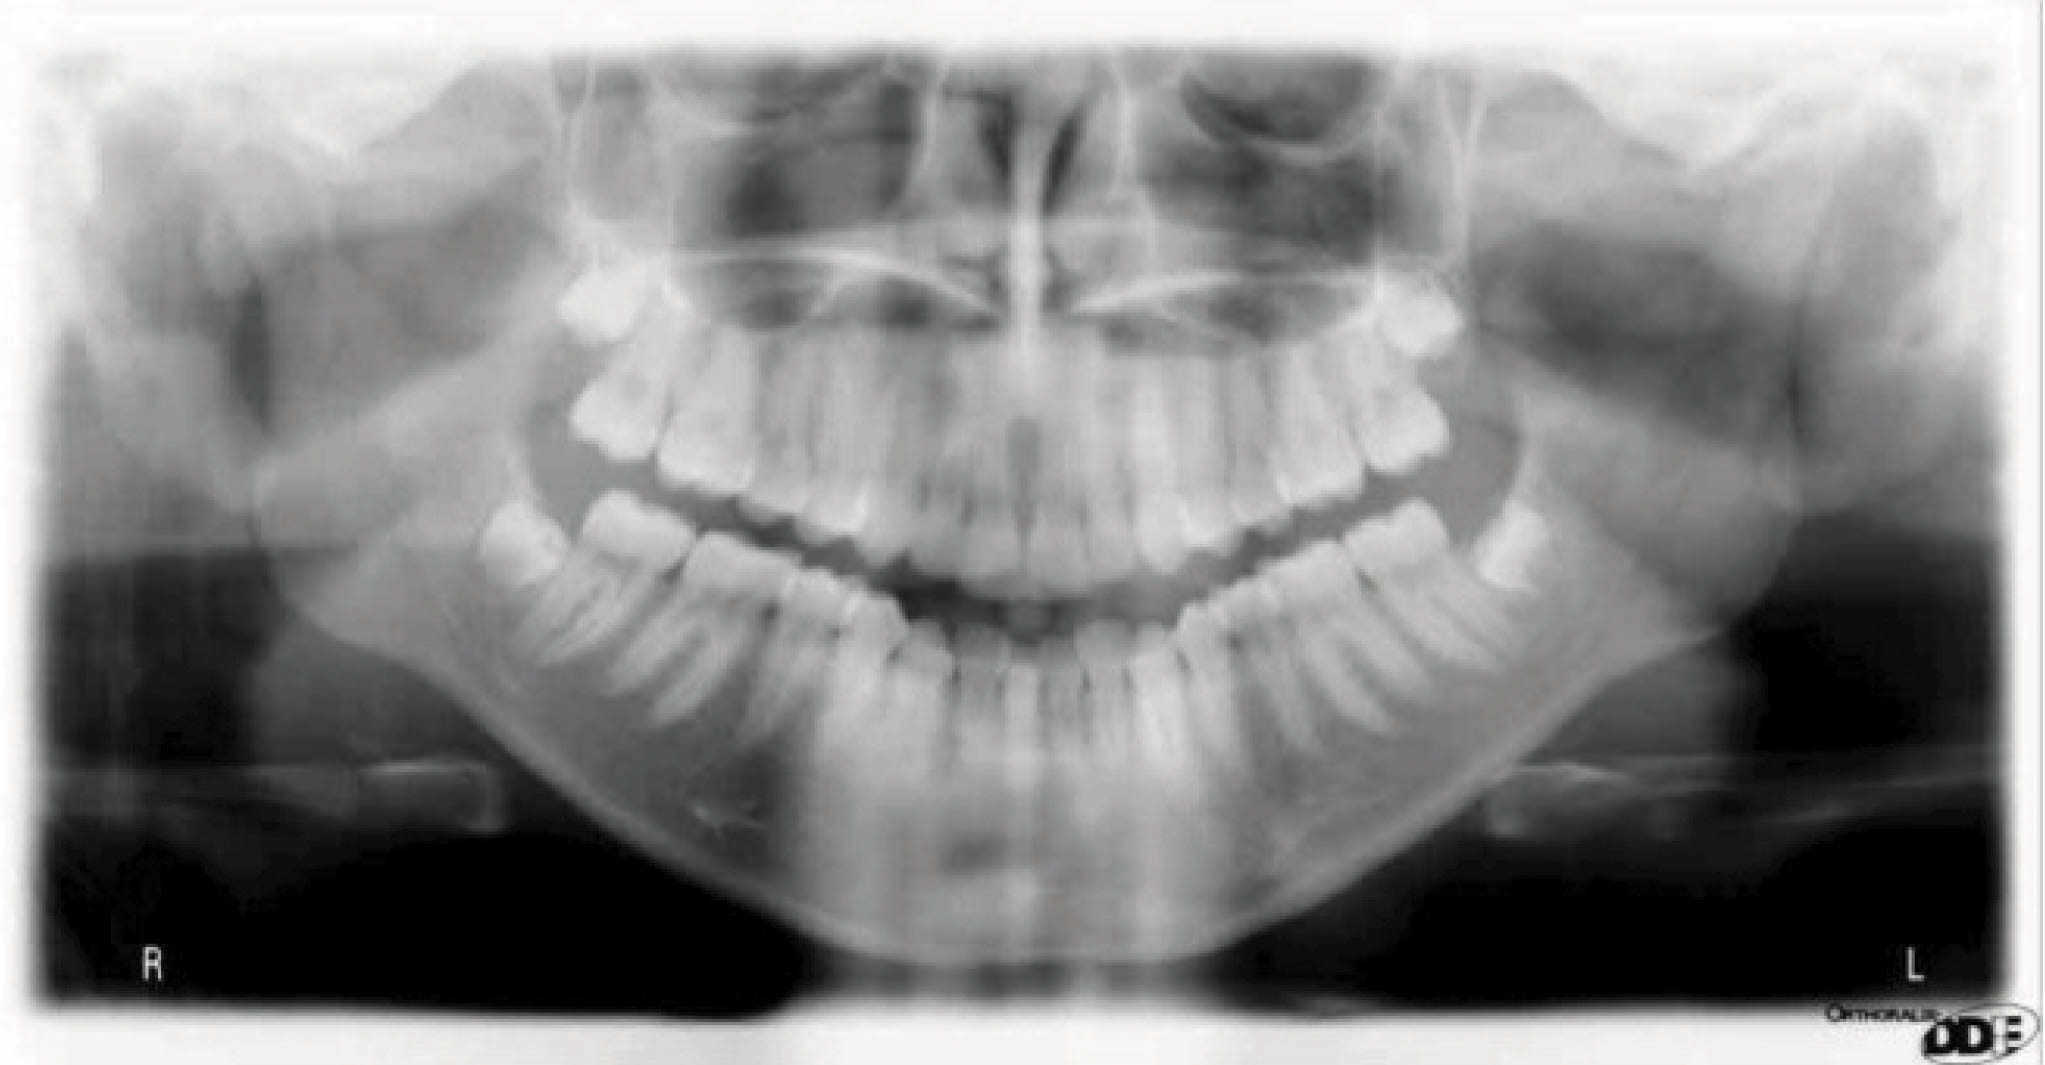

نتایج درمان (شکل 20-6) و عکس طراحی کامپیوتری (شکل 21-6) خیلی به هم شبیه شدند. عکس OPG هم طبیعی است.

شکلهای 26-6 و 27-6 نتایج درمان در قیاس با طراحی کامپیوتری را نشان میدهند. عکس OPG هم طبیعی است (شکل 28-6).